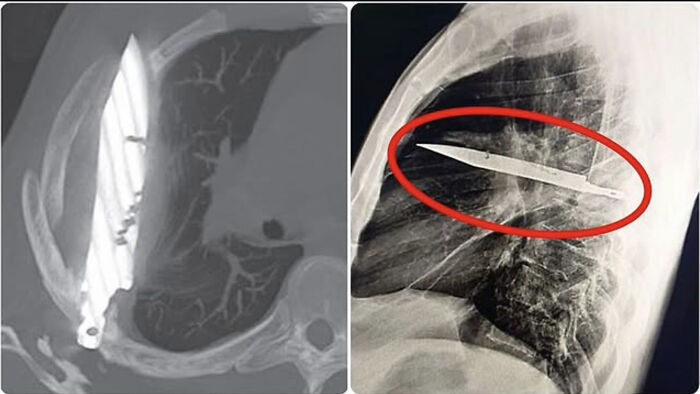

#22 A 44-Year-Old Man Arrived At The Hospital With A Strange Chest Wound. During The Examination, The Doctors Discovered That A Knife Blade Had Been Lodged In His Chest For Eight Years—without His Knowledge At All

It turns out that he was st*bbed years ago, and the wound was stitched without a deep examination. Since then, he had lived normally with no special symptoms—until the wound began to bleed, and the hidden blade was revealed in an X-ray.

The blade was surgically removed, the patient recovered, and he was discharged within a few days.